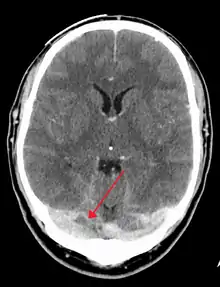

There are various neuroimaging investigations that may detect cerebral sinus thrombosis. Cerebral edema and venous infarction may be apparent on any modality, but for the detection of the thrombus itself, the most commonly used tests are computed tomography (CT) and magnetic resonance imaging (MRI), both using various types of radiocontrast to perform a venogram and visualise the veins around the brain.[3]

Computed tomography, with radiocontrast in the venous phase (CT venography or CTV), has a detection rate that in some regards exceeds that of MRI. The test involves injection into a vein (usually in the arm) of a radioopaque substance, and time is allowed for the bloodstream to carry it to the cerebral veins – at which point the scan is performed. It has a sensitivity of 75–100% (it detects 75–100% of all clots present), and a specificity of 81–100% (it would be incorrectly positive in 0–19%). In the first two weeks, the "empty delta sign" may be observed (in later stages, this sign may disappear).[11] The empty delta sign is characterized by enhancement of the dural wall without intra-sinus enhancement.[6]